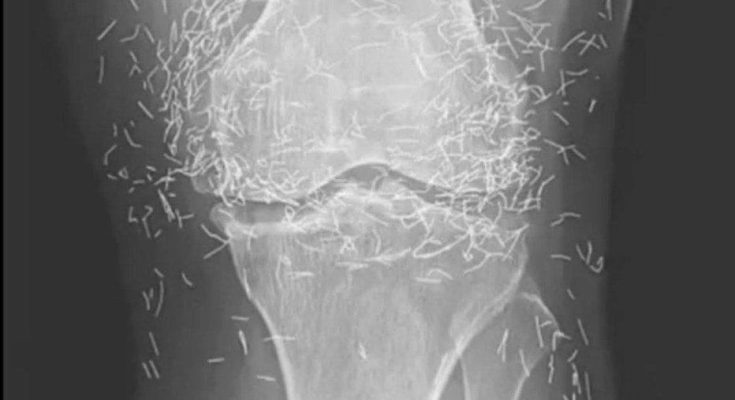

Years later, when doctors took X-rays to evaluate her knee condition, they weren’t prepared for what appeared on the images. Her knees were filled with dozens of bright, metallic flecks — tiny needles embedded deep within the joint area.

The findings were later documented in a case published by the New England Journal of Medicine.

Beyond inflammation, the needles created another problem: imaging complications. Metal objects can obscure parts of the anatomy on X-rays, making it harder for doctors to clearly assess joint damage or disease progression.